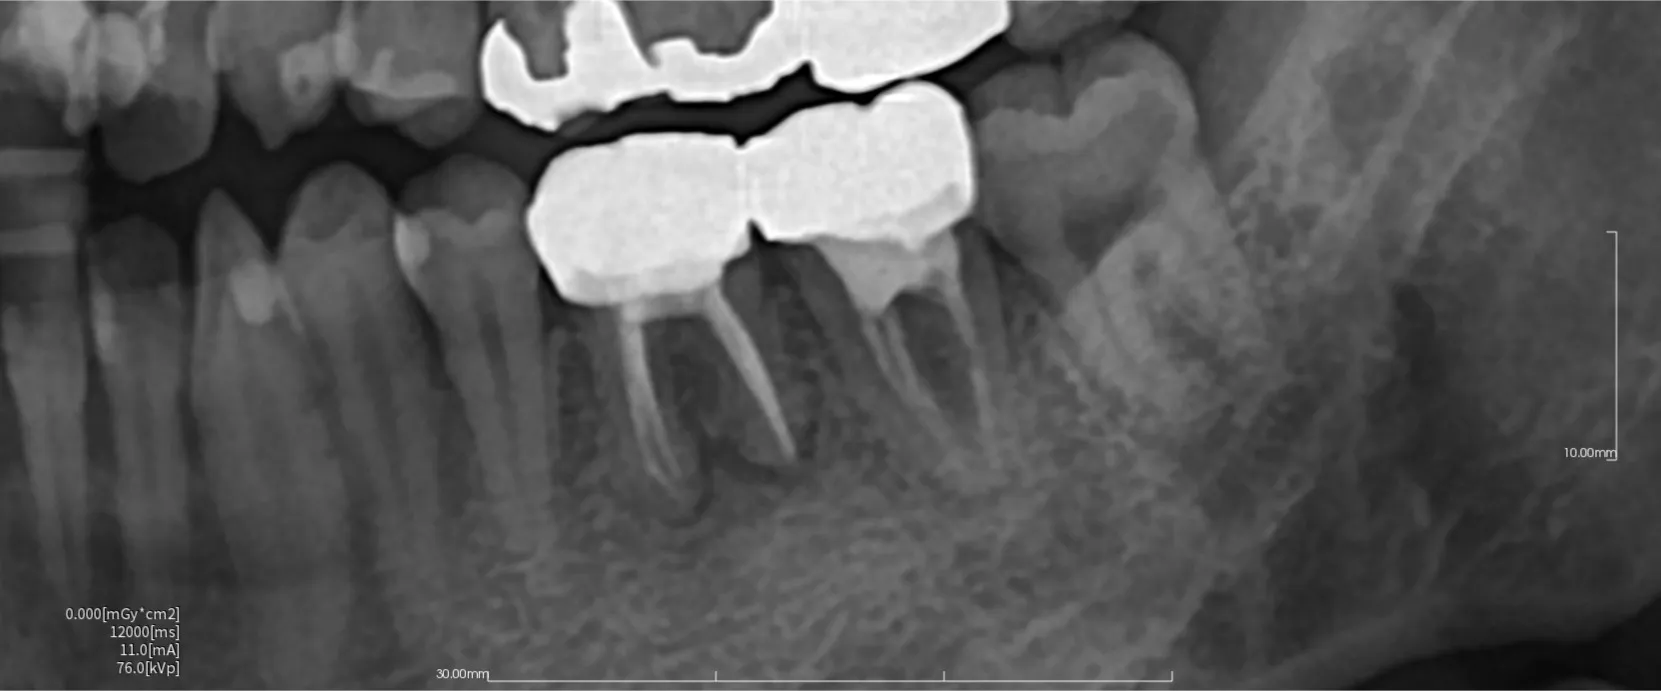

レントゲン写真で分かる!感染根管治療前後の骨の変化

今回は歯の根っこの先端にできる根尖病巣の治療と骨の変化について紹介していきます。

根尖性歯周炎(歯の根の先に膿や炎症ができる病気)の治療後に骨がどう変化するかは、治療の成否や歯の予後を判断するうえでとても重要です。

① 治療前の骨の状態

根尖性歯周炎では、

根の先の歯槽骨が溶けて黒く見える(透過像)

体が炎症を抑えるため、骨を吸収している状態

です。これは「骨がなくなった」のではなく、一時的に破壊されている状態です。